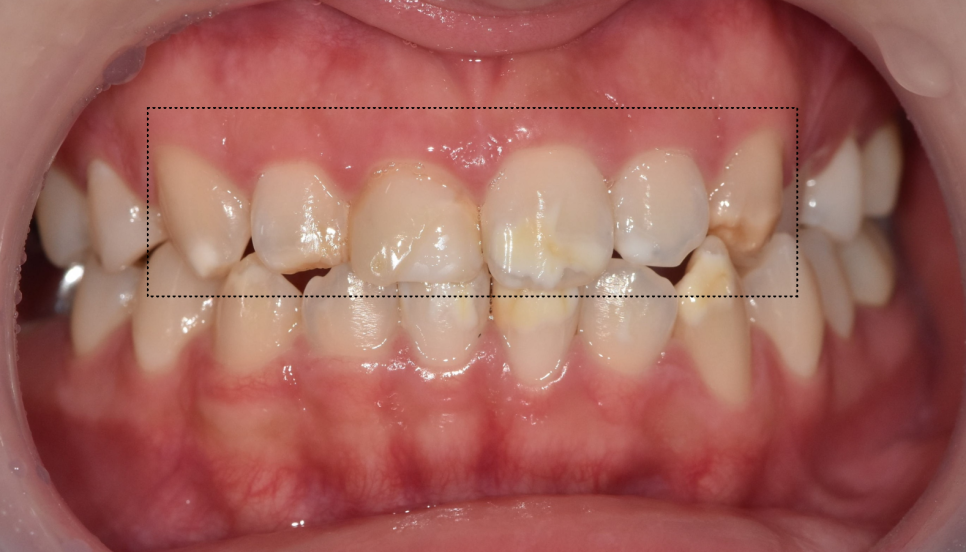

게다가 치아 길이도 전체적으로 가지런하지 않았습니다.

250503 강동구 라미네이트

아래 앞니도 하얀 반점이 여러 군데 있긴 했지만,

특히 왼쪽 아래 송곳니의 반점이 가장 도드라져 보입니다.